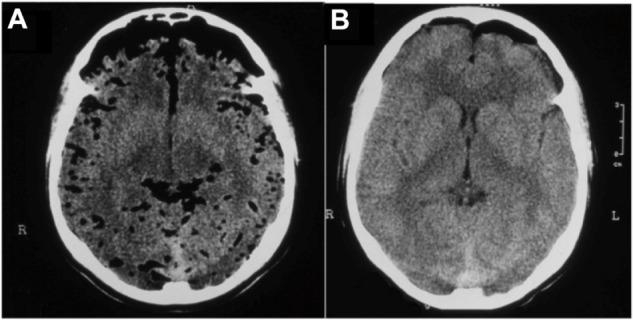

Clinical improvement was seen in all patients. In the treated group, a decrease of the gas bubble was observed on the computerized tomography scan after each session of HBO2. The treated group also experienced a lower rate of meningitis compared with the control group. The length of hospital stay was significantly higher in the control group compared with the treated group.

https://cdn.ncbi.nlm.nih.gov/pmc/blobs/4877/4199555/e41ba0b74385/tcrm-10-769Fig1.jpg